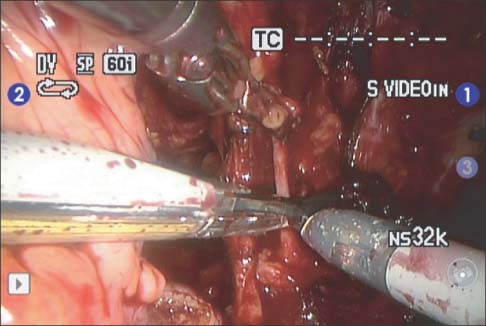

Fig. 4

Lateral dissection. Right superior vesical artery is ligated using hemoclip.

Fig. 4 Lateral dissection. Right superior vesical artery is ligated using hemoclip.